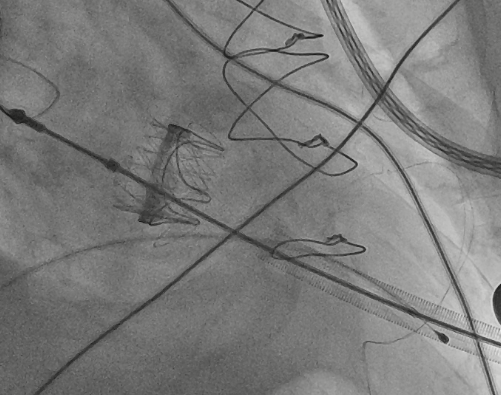

猪尾导管过瓣环平面进左心房

交换加硬导丝

扩张鞘预扩心尖穿刺点

输送器进入左室至生物瓣下方